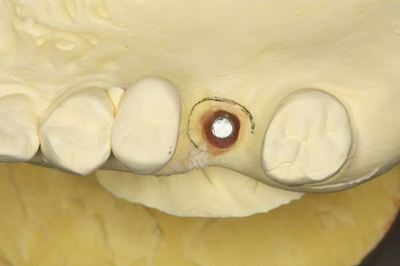

KaVo プロターevo7咬合器にマウントしました。

![]()

この部分にインプラントを植立します。